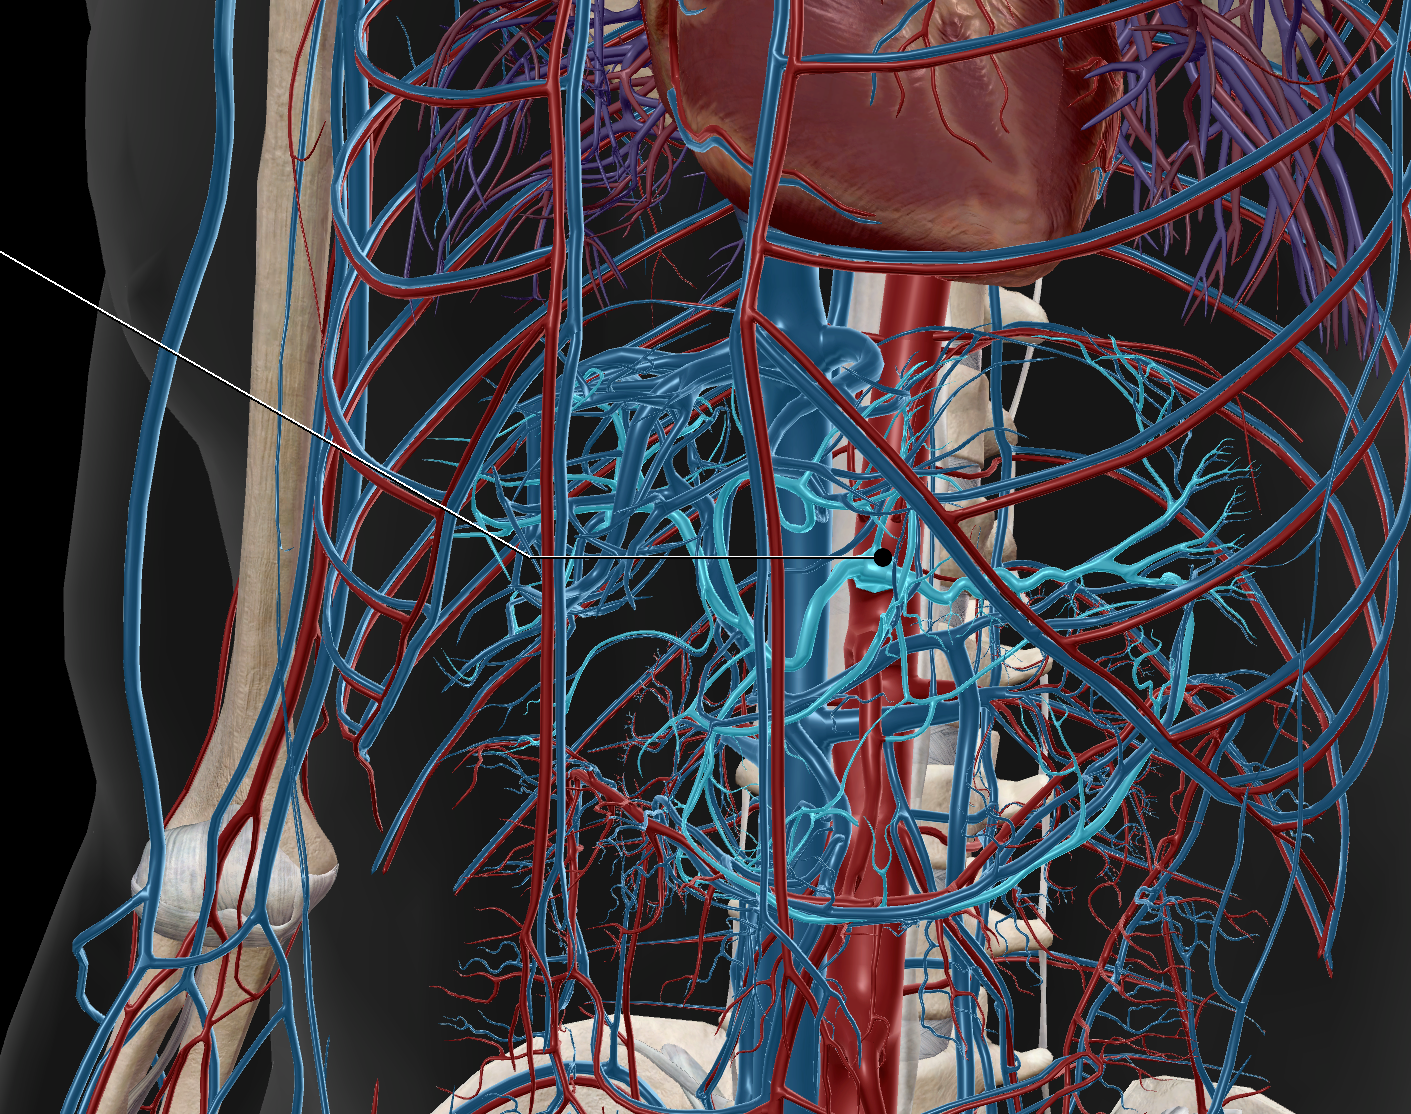

Brachial Artery

Ulnar Artery

Radial Artery

Anterior Tibial Artery

Posterior Tibial Artery

Dorsal Pedis Artery

Femoral Artery

Inferior Vena Cava

Superior Vena Cava

Common Iliac Artery

Internal Iliac Artery

Subclavian Artery

Popliteal Artery

External Iliac Artery

Inferior Mesenteric Artery

Axillary Artery

Abdominal Aorta

Superior Mesenteric Artery

Femoral Vein

Common Iliac Vein

External Iliac Vein

Internal Iliac Vein

Brachial Vein

Axillary Vein

Subclavian Vein

Radial Vein

Ulnar Vein

Superior Mesenteric Vein

Inferior Mesenteric Vein

Popliteal Vein

Anterior Tibial Vein

Posterior Tibial Vein

Great Saphenous Vein

Renal Artery

Common Hepatic Artery

Deep Femoral Artery

Peroneal Artery

Celiac Trunk